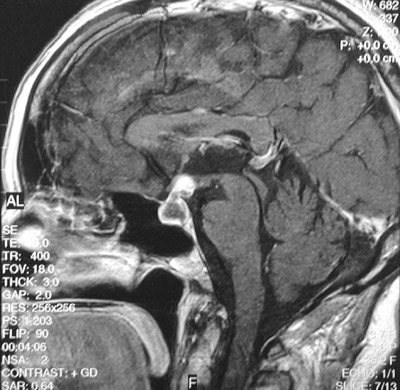

This enhanced MRI scan in sagittal view demonstrates a

cystic mass expanding the sella turcica

. This is a craniopharyngioma.